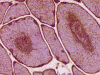

On hematoxylin-eosin stained sections, there is an increased variation of fiber diameter with many atrophic fibers intermingled with fibers of normal caliber. There is no evidence of fiber grouping or perifascicular atrophy. No inflammatory cells are present. There is also mild interstitial fibrosis (Panel A). On higher magnification, many fibers have a round concentric structure (Panel B). Irregular, centrally located depositions are also identified on modified Gomori's trichrome. The concentric nature, however, is not as obvious as in the hematoxin-eosin stained sections (Panel C). Type I and II fibers are not clearly separated in the ATPase preparation at pH 9.4. This is a common situation in chronically ill muscle (Panel D). The type I fibers are unusually dark. There is an increase in the proportion of type I fibers. The atrophic fibers are usually type II fibers. The concentric lesions are found predominantly in type I fibers (Panel E). There is an increase in PAS staining which is consistent with increased glycogen storage (Panel F). No increase in lipid content is demonstrated by oil red O (Panel G). On NADH-TR reaction, the concentric structures appear to have a clear central core that is devoid of enzymatic activity, a rim with intense enzymatic activity and a surround zone with relatively normal reactivity. These features are classic for target fibers (Panel H and I). No deficiency of laminin-2 (merosin) (Panel J) or dystrophin (Panel K) is demonstrated by immunohistochemistry. The central lesions are also immunoreactive for both laminin-2 and dystrophin. Immunohistochemistry for desmin demonstrate a core of strong immunoreactivity and also strong reaction in the sarcoplasmic membrane (Panel L and M). The target structures are also well demonstrated on semithin sections (Panel N). On electron microscopy, z-disc streaming is a common finding and they are often admixed with a substantial amount of dense granular electron dense substance (Panel O and P). There are also numerous cytoplasmic bodies characterized by radiating intermediate filaments (spheroid bodies) (Panel Q and R).